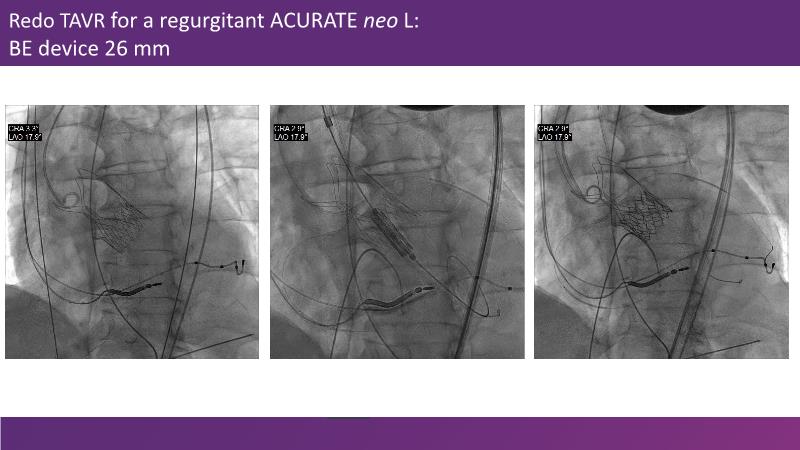

Consult this session if you want to gain insights into the effects of paravalvular leak, conduction disturbances, stroke, and permanent pacemaker issues following transcatheter aortic valve implantation. The discussion also delves into the design of transcatheter heart valves and its implications for selecting the initial valve appropriately, and the latest clinical evidence related to transcatheter heart valves.

- To understand the impact of paravalvular leak, conduction disturbances, stroke and permanent pacemaker after TAVI

- To understand transcatheter heart valve design and its implications to appropriately select the first valve